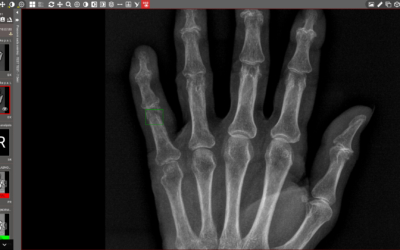

Umělá inteligence na urgentním příjmu. V Nemocnici Hořovice pomáhá lékařům určit priority

V Hořovicích přebírají první analýzu rentgenových snímků algoritmy. Urychlují práci lékařů a pomáhají jim v rozhodování.